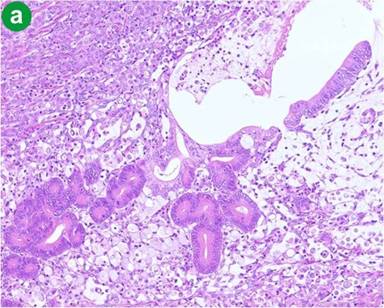

Macroscopically, the tumor measured 1.5x1.5x2 cm and the tumor surface was exposed at the papilla, showing that its surface was nodular, but there was no ulceration. Histologically, signet-ring cell carcinoma was predominant, but partially well- to poorly-differentiated tubular adenocarcinoma also existed in the lesion (Figure 3a). Signet-ring cell carcinoma arose from the ampulla of Vater, slightly involving the muscularis propria of the duodenum and infiltrating the pancreatic parenchyma. The cytoplasm of the signet-ring cell carcinoma was positive for periodic acid Schiff staining (Figure 3b). Lymphatic and vascular involvement was seen in parts, but resected lymph nodes were free from metastasis. Immunohistochemical staining was performed and both the signet-ring cells and the adenocarcinoma cells were positive for human gastric mucin (45M1) (Figure 4). Both types of tumor cells were positive for CK7, MUC1 and MUC6, but negative for CK20, MUC2 and CD10 (Figure 5). The signet-ring cell carcinoma was partially positive for CDX2 (Figure 6). The carcinoma of the ampulla of Vater was diagnosed as T3N0M0 stage IIA according to the International Union Against Cancer TNM classification. The patient did not receive chemotherapy. Six months after surgery, the patient developed pneumonia. Subsequently, the pneumonia worsened and the diabetes mellitus also deteriorated. The patient finally died from multiple organ failure due to sepsis. However, no recurrence of the signet-ring cell carcinoma was detected on repeated imaging studies.

Figure 4. Immunohistochemical findings for human gastric mucin (45M1). Signet-ring cells and adenocarcinoma cells were both positively stained. (original magnification x100). |